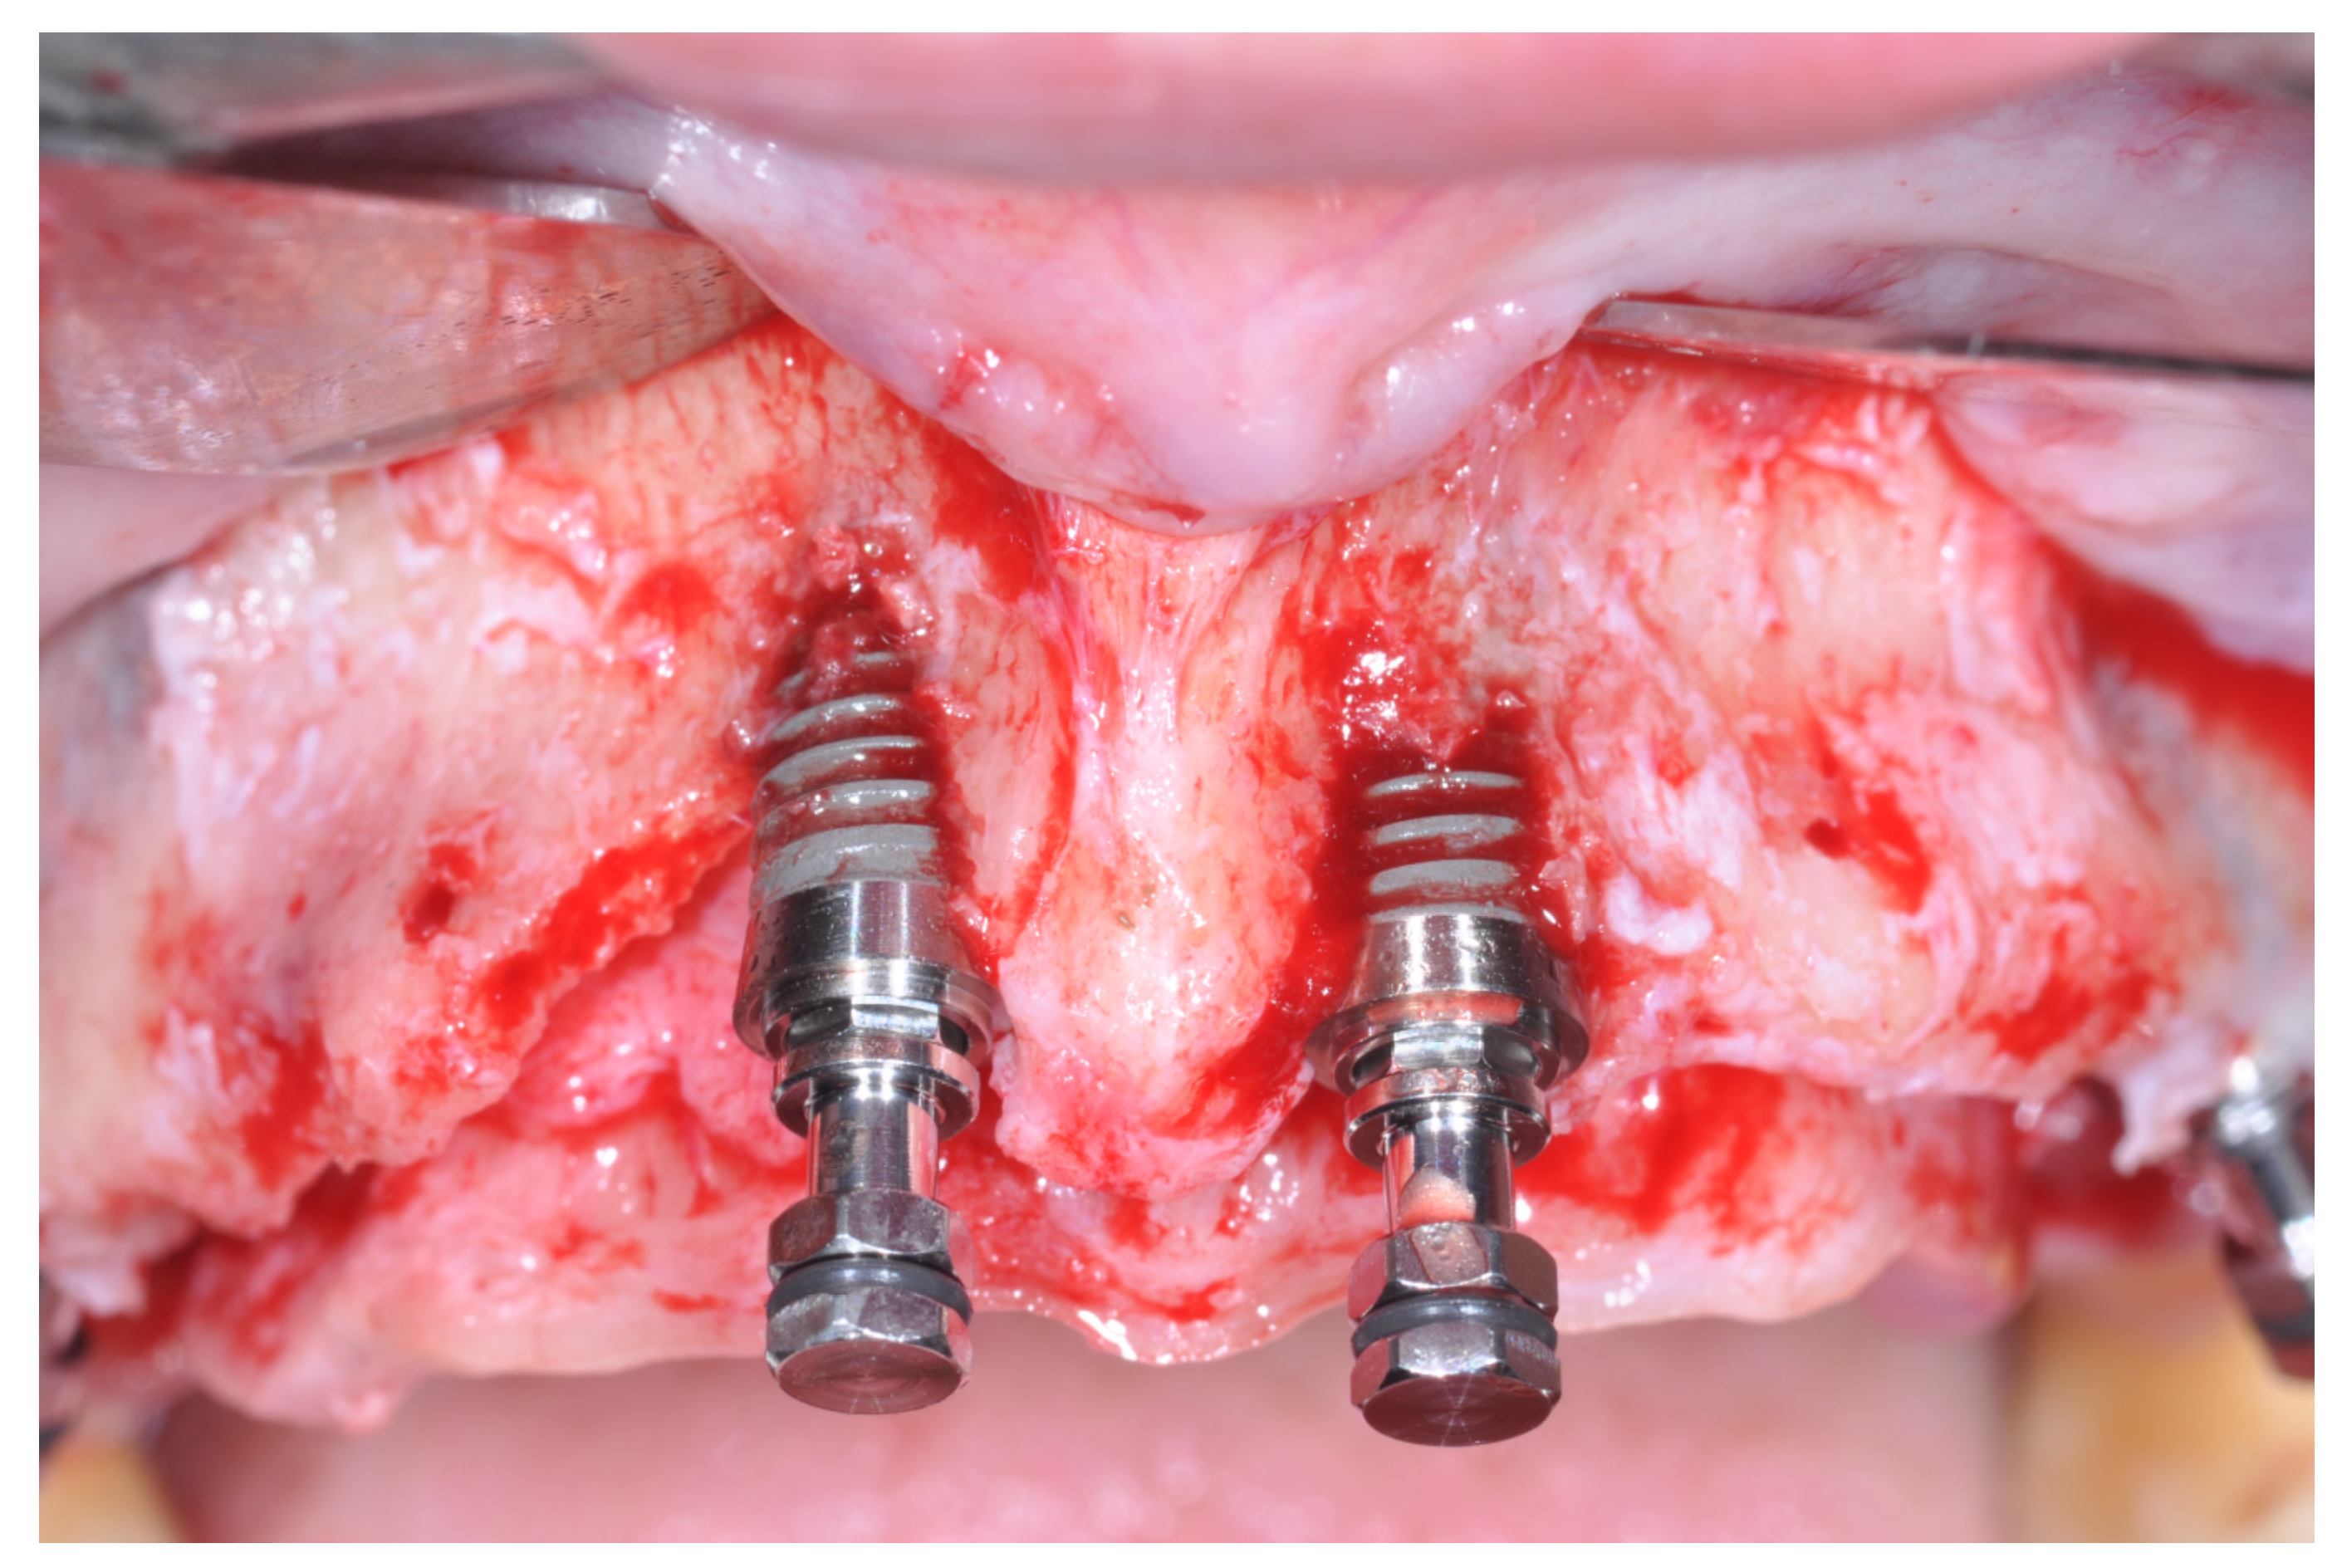

Patients rinsed with a chlorhexidine mouthwash (0.2%) for 1 min immediately prior to the intervention. Local anesthesia were administered using mepivacaine with adrenaline at ratios of 1:100,000 or 1:50,000. Crestal incisions were made with releasing incisions far away from the future membrane positioning and full thickness flaps were elevated. After the meticulous removal of all residual soft tissues in the regenerating site, copious bleeding was induced using a bone scraper (Safescraper Curve TWIST, META, Reggio Emilia, Italy) (Figure 1). A prosthetically guided implant placement was performed following the instructions of manufacturer (Thommen Medical, Grenchen, Switzerland). Only 1 patient had implants placed 9 months after bone augmentation because the initial bone thickness did not permit the primary stabilization of the implant fixtures (Figure 2, Figure 3, Figure 4, Figure 5, Figure 6, Figure 7 and Figure 8).

Figure 7. Placement of the dental implants.

Figure 9. Occlusal view after implant placement.